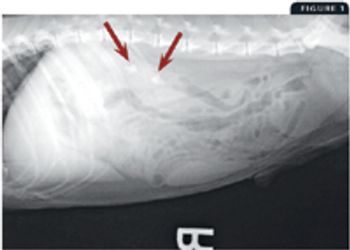

The internal medicine service at the Veterinary Medical Teaching Hospital at the University of Wisconsin School of Veterinary Medicine requested a consultation on a 7-year-old intact male Boston terrier in which pituitary-dependent hyperadrenocorticism had been diagnosed one month earlier.